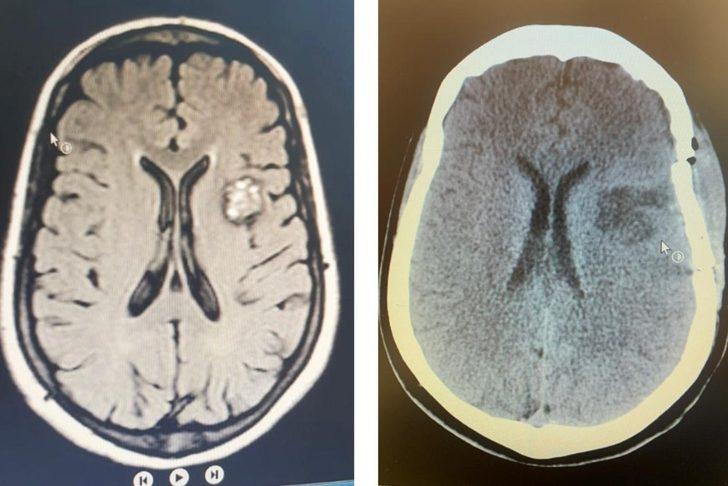

Gerçekleştirilen ameliyatla ilgili bilgiler veren Beyin ve Sinir Cerrahisi Anabilim Dalı Başkanı Doç. Dr. Utku Adilay, boyun, baş ve çenede kasılmalar ile karakterize sara nöbeti şikâyetiyle başvurduğu hastaneden, üniversite hastanesine yönlendirilen 49 yaşındaki yabancı uyruklu hastanın beyin MR incelemesinde, beyninin sol tarafında kavernom adı verilen beyin damar yumakçığı tespit edildiğini belirterek, ameliyatının da klinik bünyesinde nöronavigasyon sistemi ile başarıyla gerçekleştirildiğini belirtti. Adilay, yapılan ameliyatın üniversite hastanesi ve Balıkesir için bir ilk olma niteliği taşıdığını sözlerine ekledi.

Gerçekleştirdikleri operasyonun detaylarını anlatan Beyin ve Sinir Cerrahisi Anabilim Dalından Dr. Öğr. Üyesi Salim Katar da “Genellikle beyinde, nadiren de omurilikte yerleşen damarsal bir bozukluk olan kavernom ya da kavernöz hemanjiom dediğimiz lezyonlar, beyin kanamasına ve epileptik nöbetlere neden olabilirler. Hastamızda olduğu gibi ilaçlarla engellenemeyen nöbetler varsa veya ilaçların yan etkileri rahatsız edici derecede ise cerrahi işleme gerek duyulur. Genellikle önerilen tedavi yolu kraniotomi denilen ameliyat yöntemidir. Beyin ameliyatlarında en kritik noktalardan birisi, normal beyin dokusuna zarar vermeden en güvenli ve kısa yoldan beyin lezyonunu olabildiğince tama yakın çıkarabilmektir. Beynin derininde yerleşmiş tümör ve damar yumağı gibi lezyonların ameliyatında bu durum daha da önem kazanır. Hastamızda olduğu gibi derin yerleşimli kavernom gibi vakalarda önemli husus, damar yumağını beyne zarar vermeden en kısa ve güvenli yoldan bulmaktır. ‘Nöronavigasyon Sistemi’ beyinde hedeflediğimiz bir bölgeye hata payını en aza indirecek şekilde ulaşmamızı sağlayan ve son yıllarda kullanıma giren yüksek teknolojili, ameliyatlara yardımcı bir sistemdir. Bu tip durumlarda nöronavigasyon, ameliyat güvenliğini ve konforunu arttıran cerrahiye yardımcı bir yöntemdir. Üniversite hastanemizde gerekli olduğunu düşündüğümüz vakalarda, kritik alanlarda ve derin yerleşimli tümörlerde ve kavernomlarda, nöronavigasyon sistemini başarı ile kullanmaktayız. Sonuç olarak hastadaki kavernom, total olarak çıkarıldı. Şu an hastamızın genel durumu çok iyi, nöbetleri kesildi ve herhangi bir şikâyeti yok” şeklinde konuştu.